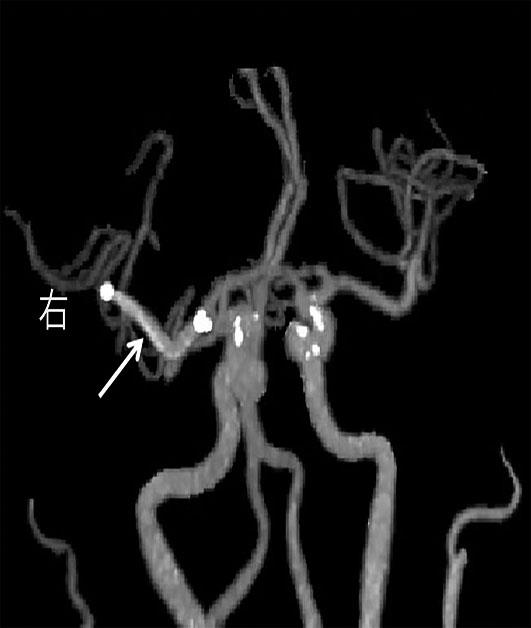

• 挽救性支架植入对取栓困难的脑动脉栓塞开通效果

摘要:目的 探究急性脑栓塞取栓失败和神经介入术中发生医源性脑动脉栓塞后补救性支架植入术的开通效果。方法 回顾性分析2020年1月至2021年11月上海交通大学医学院附属第九人民医院6例脑栓塞取栓失败和4例医源性颅内中远端动脉栓塞、接受补救性支架植入术的患者临床信息,总结患者术后血管开通情况、术后24 h 支架内血流通畅情况、出血转化和预后等情况。结果 6例急性脑栓塞取栓失败,补救性支架植入后闭塞血管全部开通(modified thrombosis in cerebral infarction score,mTICI 2b~3),术后3例出血转化(1例PH2型,2例HI2型),术后24 h支架内血流通畅5例(83%),1例未行血管造影复查;3例患者住院期间死亡。4例医源性中远端动脉闭塞中,1例为原发病为椎基底动脉高度狭窄,支架置入术中发生右侧小脑前下动脉闭塞,补救性支架置入后完全开通,术后24 h复查所有支架通畅,无脑出血,3个月预后良好,改良Rankin量表(modified Rankin score,mRS)评分1分;3例原发病为大脑中动脉栓塞,取栓术中出现同侧大脑前动脉分支闭塞,补救性支架植入后完全开通,其中1例术后24 h头颅计算机体层血管成像(computed tomography angiography,CTA)可见支架通畅,合并片状出血转化(HI2型),2例因为病重未行血管复查。结论 补救性支架植入可以快速开通取栓失败以及医源性中远端动脉的栓塞,但是疗效和安全性需进一步研究。